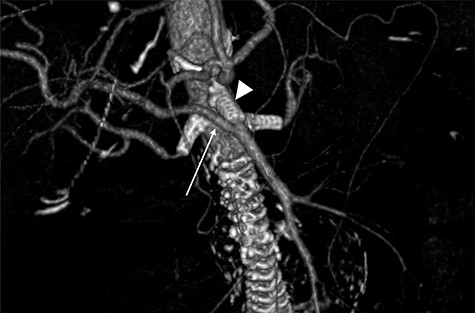

A 78-year-old gentleman admitted for elective FEVAR to treat his CT confirmed 5.7 cm juxtarenal AAA. He was not suitable for open repair and initially offered the option of no intervention due to ongoing comorbidities resulting in poor cardiopulmonary function; however, he was keen to proceed with surgery. From pre-implant planning CT angiogram (CTA), infrarenal endograft was unsuitable for EVAR due to reverse conicity and unhealthy infrarenal aortic neck (Fig. 1); therefore, FEVAR was chosen. RRHA from SMA was also seen in pre-operative CTA but not reported (Fig. 2).

Pre-operative CTA showing healthy SMA (arrowhead) with RRHA (arrow).